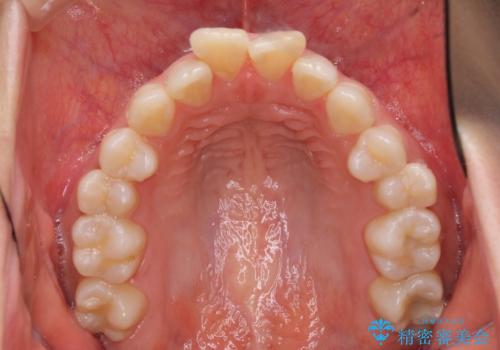

- 上の前歯の飛び出した感じと上下前歯のデコボコを気にして来院された患者様です。

叢生が強く、口元の突出感もあるため、上顎左右第一小臼歯4本を抜歯することとしました。

奥歯の咬み合わせ改善が必要なため、ワイヤー装置による矯正治療を強くお勧めしまたが、本人の希望でインビザラインにて治療を開始することとなりました。

インビザラインでの抜歯治療は予定通りに治療が進まないことが多いため、必要であればワイヤー矯正に切り替えるとお伝えした上で治療を開始しました。